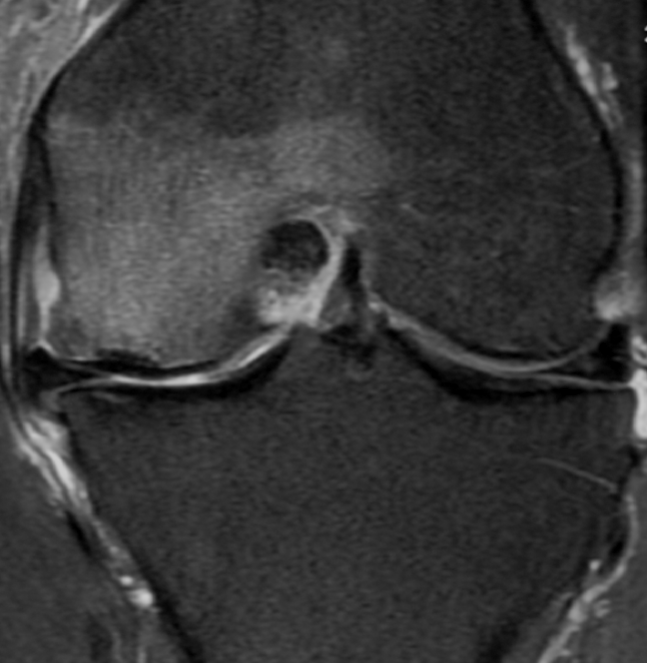

MRI

May be normal in early stages

TI

- low signal areas in subchondral region

T2

- low signal

- surrounding high intensity signal secondary to oedema

MRI

More extensive involvement through knee